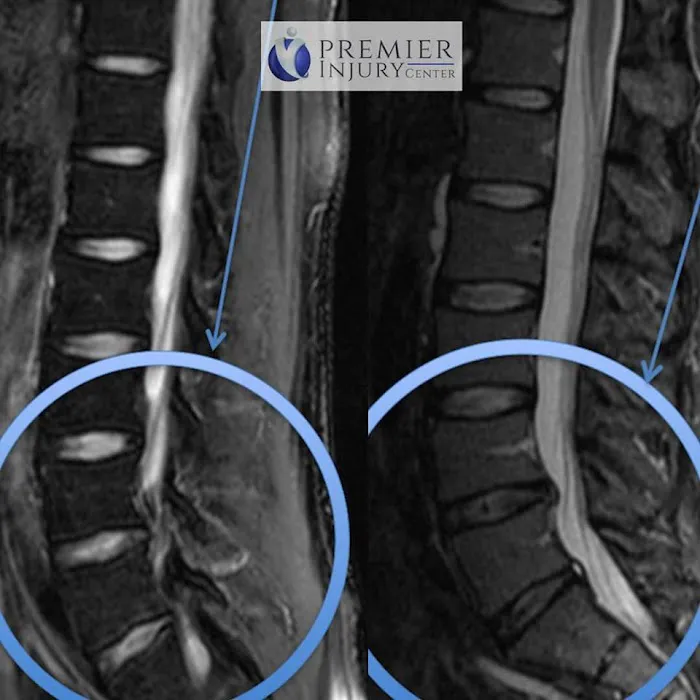

Jan 16, 2024 · Ruby AhenkorahAs a former college athlete with multiple injuries Dr Syam and his medical team have been great to my recover and to my functionality. I have had 2 hip surgeries, fractured back, spinal stenosis L1 through L5 and several other injuries. I recently had the stem cell injection in my lower back and its been about a year since I have it done. I was skeptical at first however I feel great, I am able to do things that I haven't been able to do in over 10 years. I am grateful for this group and would highly recommend their services to any patient who is in pain.